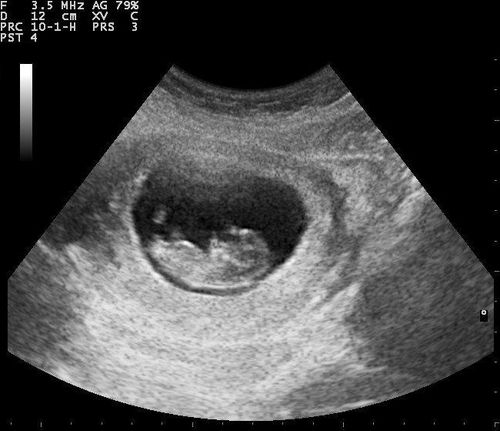

Cháu mới có bầu 5 tuần và siêu âm phát hiện tụ dịch diện rộng, vị trí dưới túi thai kích thước 24×17mm và túi thai bờ mỏng. Bác sĩ cho cháu hỏi thai 5 tuần tụ dịch dưới túi thai kèm túi thai bờ mỏng có sao không? Cháu cảm ơn bác sĩ.